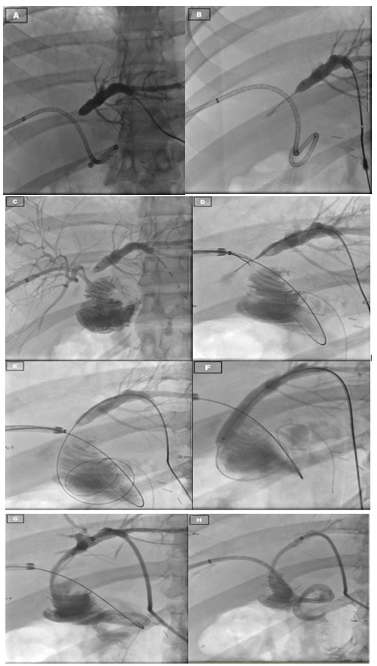

A 29-year-old male presented to an outside hospital for evaluation for abdominal pain and was diagnosed with acute cholecystitis. The patient was taken to the operating room nine days prior to presentation at our hospital for a laparoscopic cholecystectomy. Though the dissection was difficult, the case proceeded uneventfully and the patient was subsequently discharged post-operatively. The patient returned to the outside hospital on post-operative day 7 with high fevers and had a collection seen on ultrasonography, which was then identified as a bile duct leak on HIDA scan. An ERCP was performed at this time, but the biliary duct could not be cannulated due to an obstruction. The patient was brought back to the operating at this point for an exploratory laparotomy. After exploration, the surgeons identified a bile leak, but could not identify the proximal bile duct. Intra-operative cholangiogram was performed through the distal duct, which revealed flow into the duodenum, but the proximal duct could not be identified. Given the complexity of the anatomy and the case, the patient was transferred to us for further surgical management. On arrival, the intraoperative cholangiogram from the outside hospital was reviewed and a diagnosis of congenital agenesis of the common bile duct as suspected as flow through the ligated cystic duct went directly into the duodenum. At this time, Interventional Radiology (IR) was consulted to perform at PTC to review the biliary anatomy and create a road map for further repair. However, only the right hepatic system could be catheterized as the left hepatic duct was too small (Figure 2a). The cholangiogram through the right PTC showed a large bile leak, but no extra-hepatic ducts could be identified at all. Given these findings, the patient was then taken to the operating room for exploratory laparotomy. Upon examining the surgical site, the distal bile duct was significantly dilated to 9-10 millimeters in diameter. Proximally, the right PTC catheter placed by IR was emerging from the intra-hepatic right biliary system and further exploration did not reveal any intra-hepatic biliary ducts from the left or any extra-hepatic ducts. A complete portahepatis lymphadenectomy and dissection with skeletonized hepatic artery and portal vein was performed in an attempt to localize the left intra-hepatic duct and right extra-hepatic duct to no avail. It was suspected that the patient had variant anatomy with common bile duct agenesis with the left hepatic duct connecting to the right hepatic duct high in the liver parenchyma. Given this, continuity was restored to the biliary tree via a hepaticoportal enterotomy, or Kasai procedure. The tissue around the porta hepatis and the right PTC wrapped around an enterotomy in a two layer anastomosis. The patient was managed for the first three post-operative days in the intensive care unit before being transferred to the surgical floors where his recovery continued before ultimately being discharged. Subsequent follow-up appointments revealed adequate patency of the right-sided biliary catheters and ultimately, dilation of the left sided biliary system to permit cannulation and drainage into the intact hepaticoportal enterostomy (Figure 2b and 2c). Clinically, the patient remains stable and with unremarkable laboratory results 18 months from surgery.

Figure 2c: Follow up cholangiography several months after surgery for Case 2. Pictures as labeled: A - Dilated left hepatic duct system, B - catheter passing through severely stenotic region of left hepatic duct, unable to float into common hepatic duct, C - right hepatic duct cholangiogram with flow into jejunal limb, D - Removal of right PTC catheter over wire, insertion of left hepatic duct wire, snare of left hepatic duct wire through right hepatic duct, E - left hepatic duct wire dragged through common hepatic duct into duodenum via right hepatic duct snare, F - balloon dilation of stenotic area of left hepatic duct, G - insertion of PTC catheter into left hepatic duct, H - reinsertion of right PTC catheter.